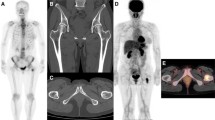

Figure 1 shows representative examples of FDG PET images obtained in study patients. The images in the upper frames illustrate a patient with decreasing FDG uptake after therapy. The patient’s initial FDG PET scan demonstrated a maximum SUV reading of 5.2 at the index lesion located in the lumbar spine at the level of L4. Following treatment, the SUV reading decreased to background levels of 2.2. The images in the lower frames of Fig. 1 illustrate an increase in FDG uptake with treatment. Table 2 summarizes initial maximum SUV values and FDG PET changes for the cohort. The average pre-treatment SUV was 5.9. The average SUV change during treatment was a decrease of 2.2, ranging from a decrease of 9.2 to an increase of 2.8. The average percentage change in FDG PET was a 33% decrease in SUV.

Serial FDG PET imaging examples. The upper frames illustrate representative coronal images from serial FDG PET scans on a patient with decreasing FDG uptake after therapy. The index lesion in the lumbar spine at L4 demonstrates a SUV of 5.2 on the initial scan (upper left). Following treatment, the SUV reading of the L4 lesion decreased to background levels of 2.2 (upper right). The lower frames depict coronal images from a patient with increased FDG uptake after therapy. The index lesion in the thoracic spine increased from an initial SUV of 3.4 (lower left) to a post-therapy SUV of 8.0 (lower right)